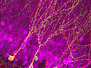

Slipping its Tethers

An estimated 34 million people worldwide currently live with AIDS, a disease of the immune system caused by the virus HIV. Infecting the white blood cells that normally defend us against disease, such as lymphocytes and macrophages, this virus also neutralises the body’s antiviral weapons at the molecular level. One such weapon is tetherin, a protein that binds to virus particles and tacks them to the cell membrane, preventing their release into the bloodstream. Pictured are macrophages (nuclei stained blue) in which the immune response has been activated. Tetherin (in green) is seen alongside a protein (in red) that’s highlighting the membrane compartments where HIV particles are assembled before release. But HIV evades tetherin’s grasp with a weapon of its own – a protein called Vpu – which stimulates degradation of tetherin. This adaptation may have been a key step in the successful spread of HIV-like viruses in primates to human hosts.